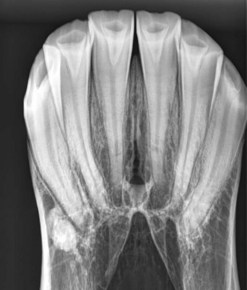

Intra-oral radiographs (Fig 13.2)

The smallest cassette available should be used, and the patient must be sedated to prevent damage to the cassette. A low exposure is required compared with that needed to image the cheek teeth. The cassette should be placed between the incisors, as far caudally as possible, and held in position using long-handled hoof trimmer testers or a similar instrument, with the cassette held at a distance from the assistant.1 The X-ray beam is directed at 60–80° from the dorsal plane (which runs parallel to the hard palate), depending on the conformation of the incisors, using a rostrodorsal–caudoventral oblique to image the maxillary incisors/canines and a rostroventral–caudodorsal oblique to image the mandibular incisors/canines. The beam should be centered on the Triadan 01s (central incisors), and collimation should include the rostral and lateral aspects of the lips. If necessary, the X–ray beam can also be angulated slightly from left to right to try and highlight the apices of incisors at the edges of the incisor arcade without superimposition of adjacent teeth (Figs 13.3 & 13.4).

Fig. 13.3 Intra-oral view of the lower incisors of a horse with abnormally small and fractured 01s and 02s. This radiograph was taken with the X-ray beam perpendicular to the frontal plane. Note there is superimposition of the apices of the 02s, 03s and canines.